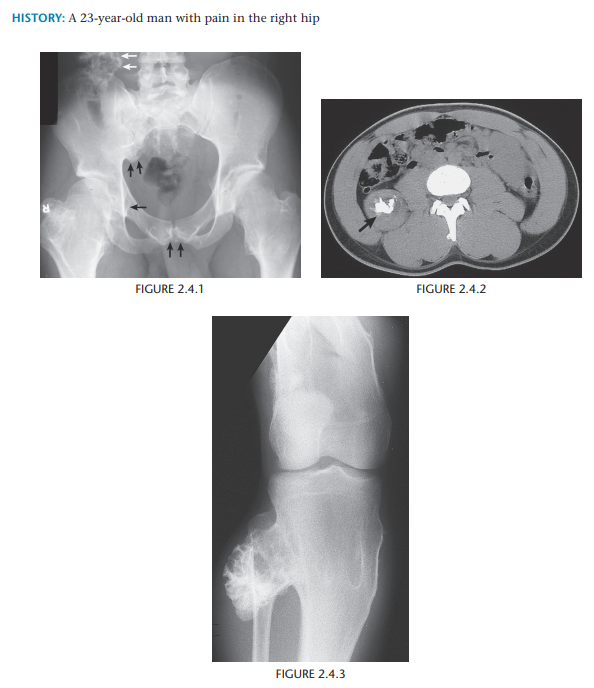

Mulitple Hereditary exostosis

Multiple hereditary exostosis

Maffucci syndrome (i.e., multiple enchondromatosis with soft-tissue hemangiomas)

Multiple enchondromas + soft tissue hemangiomas